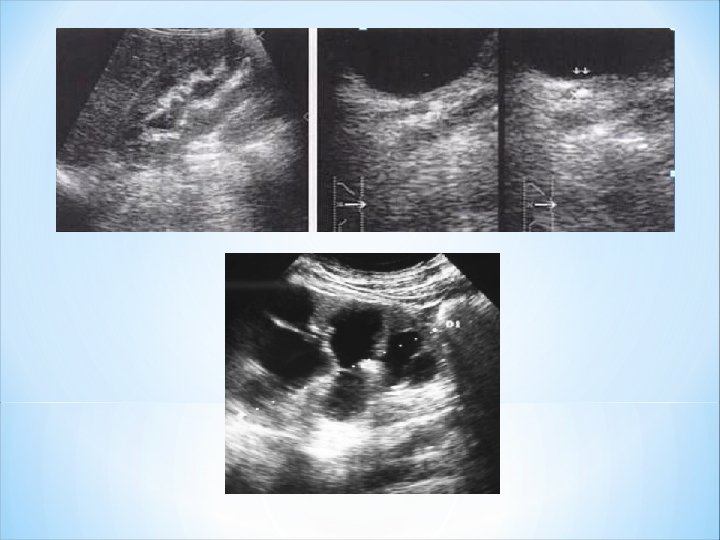

Echographie : faux négatifs : 21 à 35 % si échographie réalisée seule. -Affirmer la dilatation des cavités pyélocalicielles et de l'uretère ( tiges calicielles dilatées, bassinet > 3 cm de diamètre antéropostérieur). -Préciser le niveau de l'obstacle et son type -Evaluer le parenchyme rénal, en particulier son épaisseur qui reflète la détérioration rénale et l'ancienneté du processus. -Une extravasation = liséré anéchogène périrénal ou collection périrénale Doppler pulsé et couleur du rein Calcul des indices de résistances. Jet urinaire.

d-Hydronéphrose infectée et pyonéphrose L’échographie : hydronéphrose ou une urétérohydronéphrose souvent avec calcul(s) : rétention d'urine purulente dans des cavités distendues par une obstruction sous-jacente. ØContenu échogène des cavités dilatées. ØHydronéphrose infectée: parenchyme rénal d’épaisseur normale. ØPyonephrose: Amincissement, voire la disparition du parenchyme rénal. TDM: densité cavités dilatées élevée 25 à 30 U. +++ponction échoguidée: diagnostique et thérapeutique.